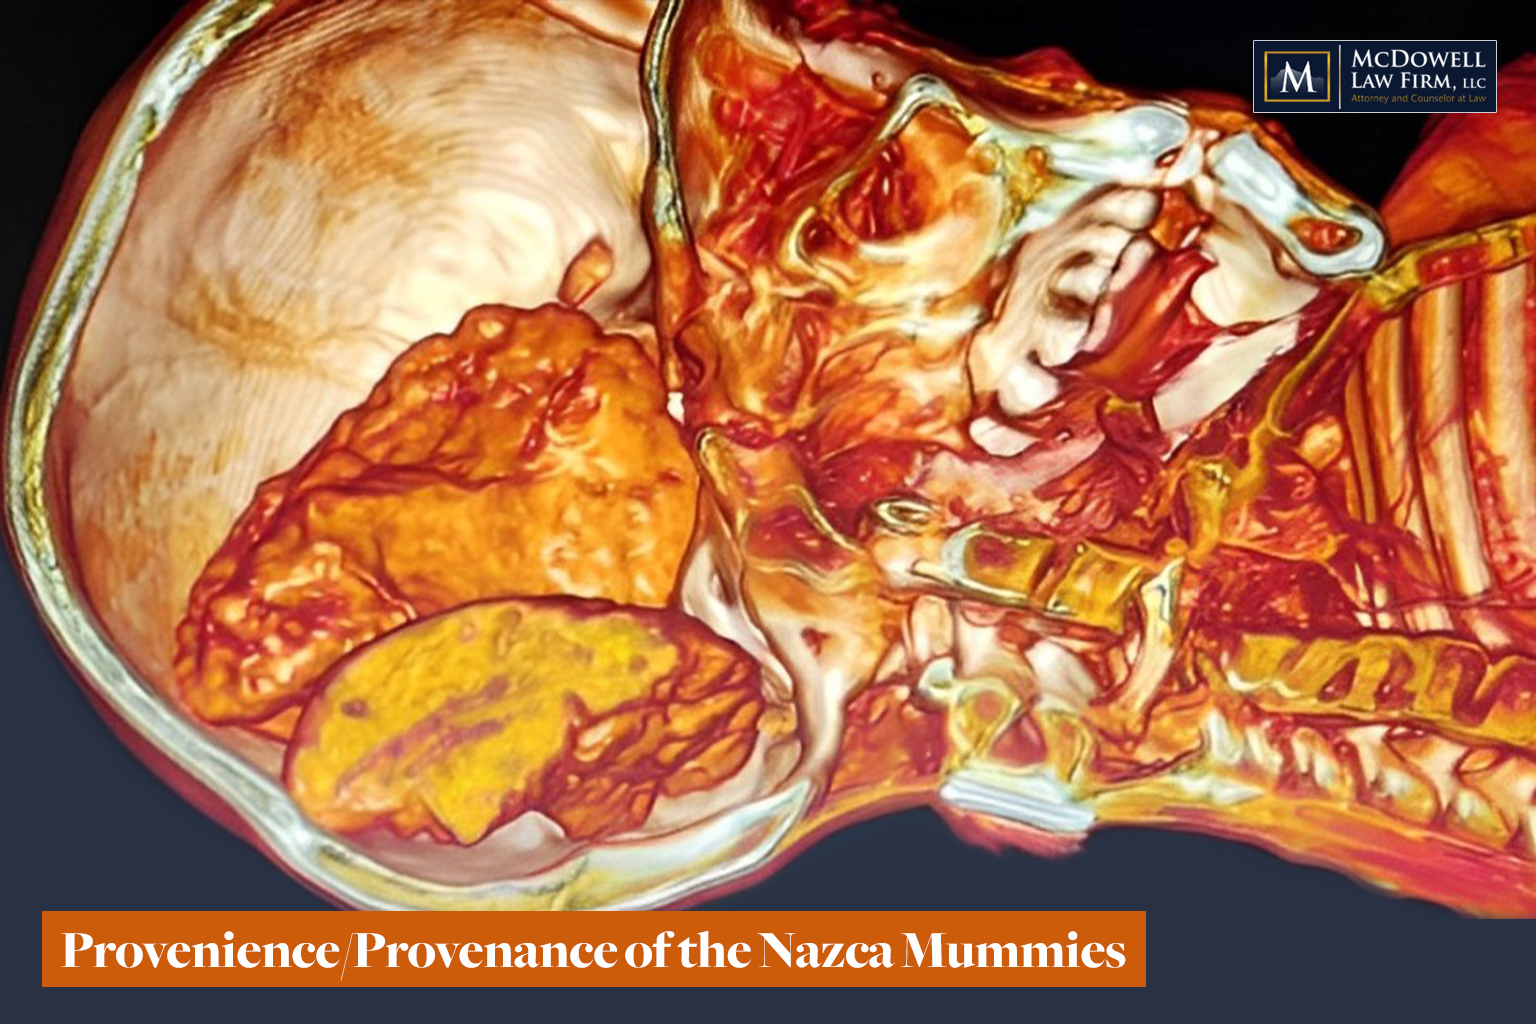

Do these Nazca mummies represent the true form of a once-living biological species, or are they something else entirely?

Are these bodies works of art or intentional hoaxes made of a mish-mash of animal bones? Are they human bodies that have suffered the indignity of ancient or modern modification? Maybe some of both?

Or do these bodies represent the remains of formerly unknown species (plural) that once lived and breathed in the Nazca region?

If you’ve been following this story, you would know that many educated professionals and doctors believe these bodies to be the remains of real organisms. At the recent press conference in Lima on April 4, 2024, you heard from Dr. David Ruiz, a plastic surgeon and forensic specialist from Peru. You also heard from Dr. Jose Zalce Benitez, a Mexican Navy Forensic doctor. These doctors have resumes a mile kilometer long, and they have examined these bodies in person, with CT scans, X-rays, tomography, etc. They have not detected manipulation of the bodies.